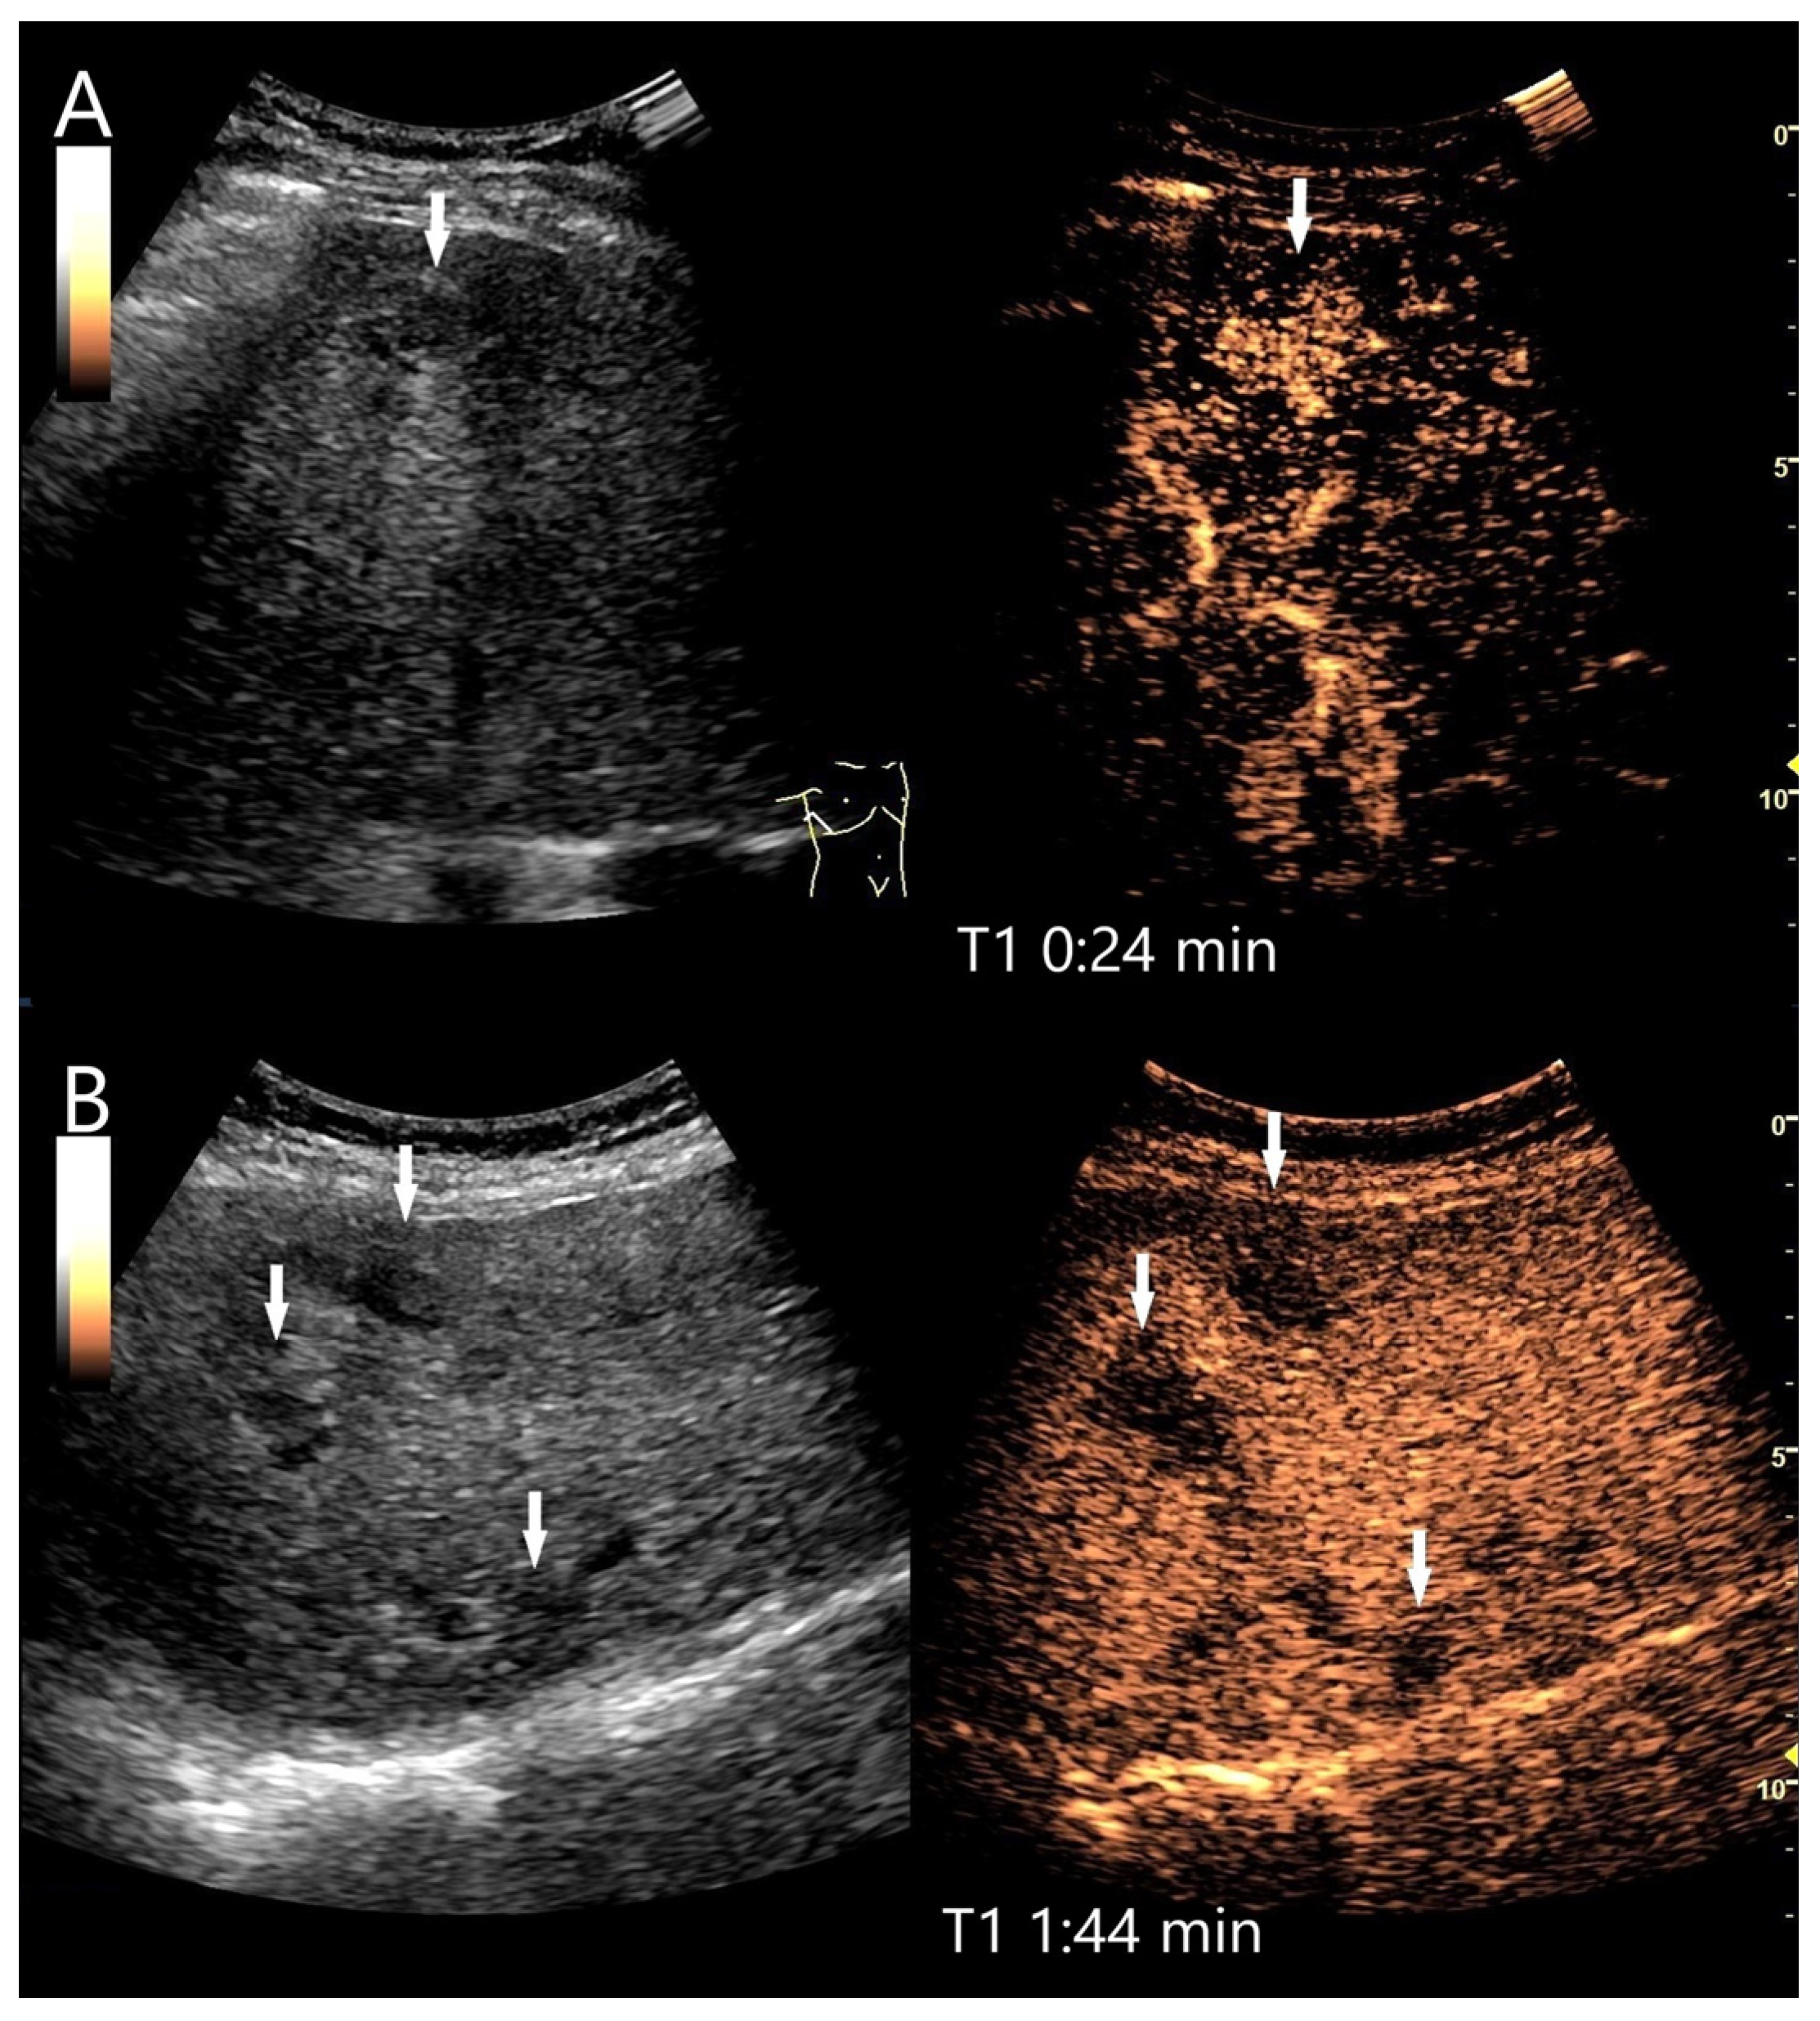

| Hemangioma | Hyperechoic, beyond liver veins, hypoechoic in steatosis and with shunts. | Peripheral globular enhancement, centripetal filling. Rapid homogeneous filling in shunt hemangiomas. | Hyperenhancement and isoenhancement. | Permanent video loops with destruction of the UCA bubbles and slow refill. Fibrosis. |